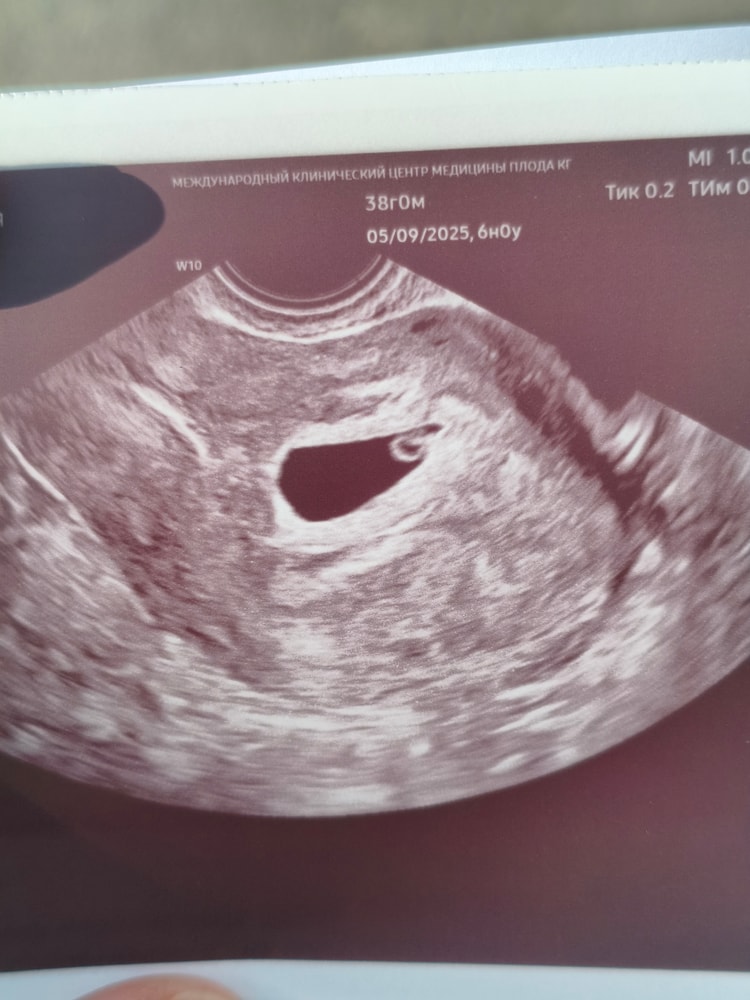

УЗИ, КТГ, доплерВсем доброго время суток! Наконец то попала на первое свидание со своим 3 "пирожочком". По месячным 6 недель ровно, по ктр 5.5. "Домик" конечно большой кажется, что аж эмбриона в углу еле видно😅 сердцебиение определили, пульсацию показали, но не слушали. У меня прям каждая последующая беременность идеальнее предыдущей (пока что тьфу-тьфу)🤭 домой с УЗИ аж пархала как бабочка😁

Давайте носить вместе😄🤝 у меня как будто бы срок тоже 6 недель, но ктр всего 3,3 мм. Сил и терпения нам и нашим крошкам🤞🌞